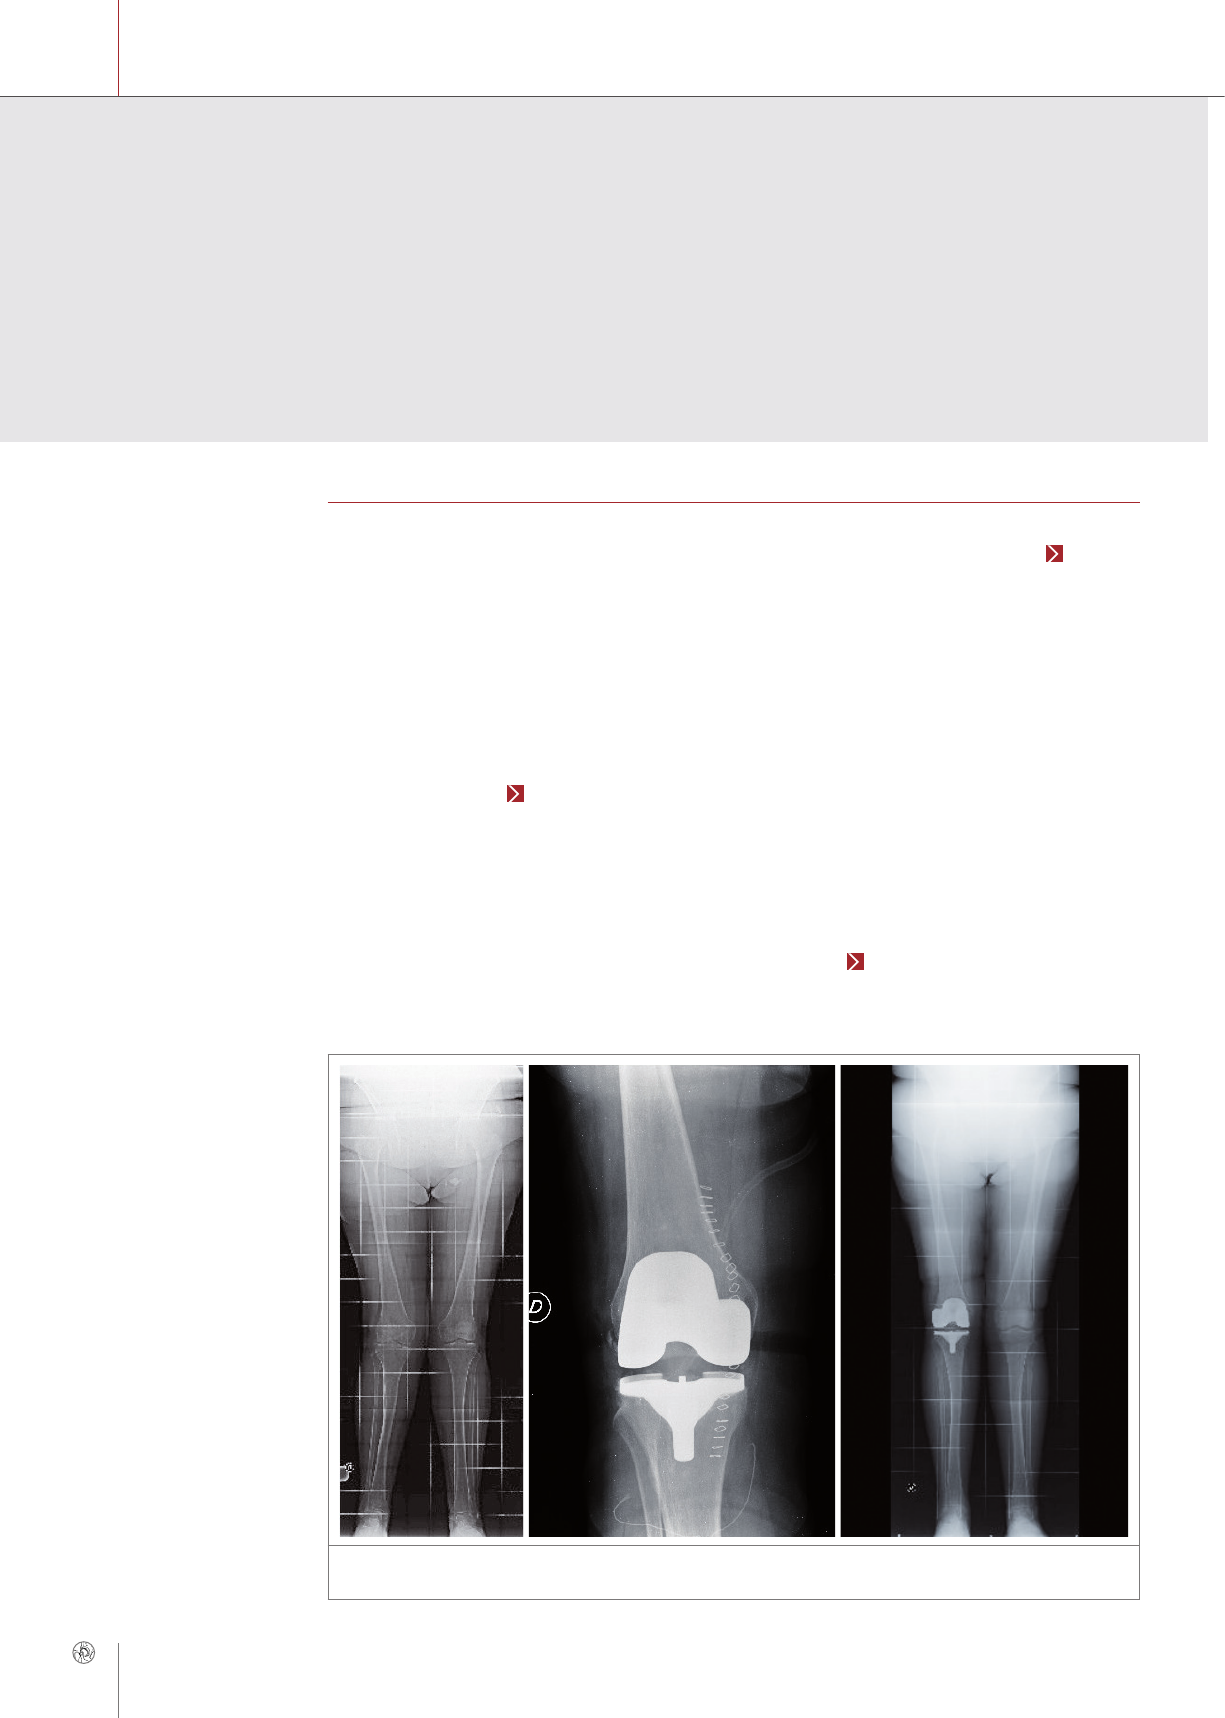

Primary TKR for advanced arthritis

Diagnosis

A 68-year-old woman with a history of hyperten-

sion, coronary artery disease, and multiple allergies

(asthma, dust). The patient had had a painful right

knee due to arthritis for two years. The preopera-

tive X-rays clearly showed severe valgus osteoar-

thritis with involvement of the lateral compartment

and patellofemoral joint as well as a lateralization

of the mechanical axis (Fig. 1a).

Indication was for primary TKR with a Multigen

Plus ceramic knee implant (Lima) to avoid cross-

linked reaction due to suspected metal allergy.

Therapy

Surgery was performed via a mini mid-vastus ap-

proach. Replacement of the knee was done with a

fixed Ti tibial plate (size 2) and a ceramic CR femoral

component (Biolox®delta Multigen Plus, size 3) and

and a poly liner with a height of 12 mm (Fig. 1b).

Postoperative therapy included a femoral nerve

block (naropin) for analgesia and fast rehabilitation

of the knee: The patient began to exercise to regain

range of motion on the first postoperative day, and

she walked with two canes on the second postoper-

ative day. She took non-steroidal anti-inflammatory

drugs (indomethacin) for 3 weeks, as did the other

patients who underwent TKR.

After 4 weeks she was able to do without one cane

and she had very mild pain, which had disappeared

at the 3-month follow-up. The range of motion was

0–115° and the excellent results were confirmed at

the last follow-up. X-rays showed a good restoration

of limb alignment and no radiolucent lines at 6 years

of follow-up (Fig. 1c). The final clinical KSS was

98 points (excellent), the final functional KSS was

100 points (excellent), and the final OKS was 47.

CASE REPORT 1

Figure 1: Primary TKA 68-year old woman: a) lateralization of mechanical axis preoperative, b) postoperative situa-

tion, c) follow-up after six years: good limb alignment (© Benazzo)

a b c